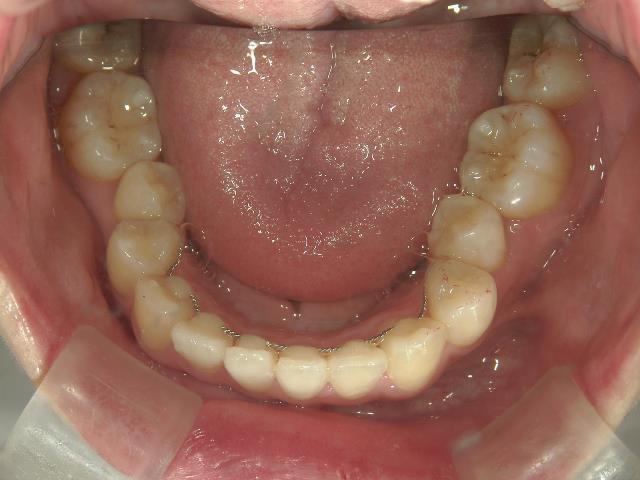

矯正歯科 治療前

矯正_灰色.pngno.8_8495_治療前_下.jpg矯正_灰色.png